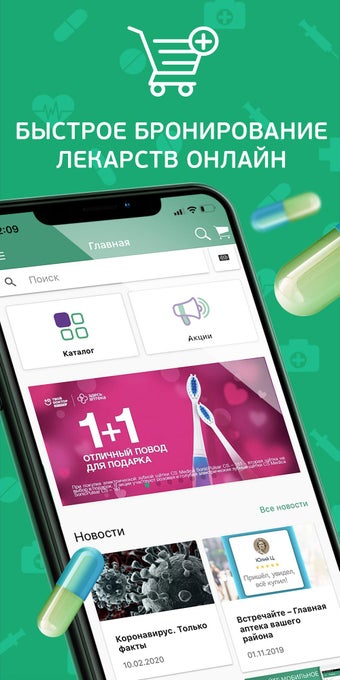

HERE PHARMACY là một nhà thuốc trực tuyến Nga giúp bạn đặt hàng tất cả các loại thuốc từ các nhà thuốc. Dịch vụ của chúng tôi cho phép bạn:

- Tìm kiếm các loại thuốc trong tất cả 790+ nhà thuốc của mạng lưới của chúng tôi

- Đặt thuốc từ bất kỳ nhà thuốc nào của chúng tôi

Với vài cú nhấp chuột, bạn có thể mua bất kỳ loại thuốc nào bạn cần cho bản thân hoặc gia đình của mình, bất kể loại thuốc đó.